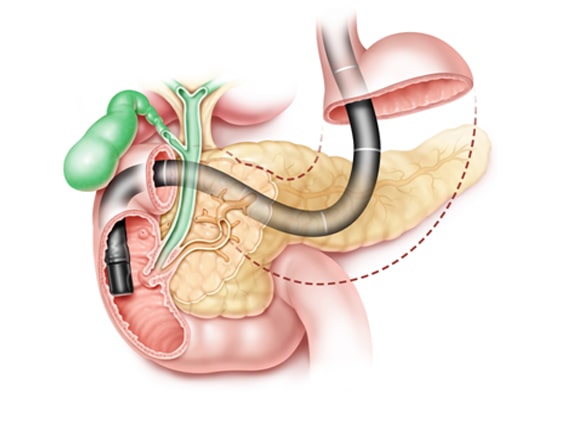

Cholangioscopy

Diagnostic and therapeutic intervention of the bile ducts. It is one of the noninvasive...

ERCP is a procedure that is adopted to diagnose the disease-related liver, gallbladder, pancreas, and biliary system. With a help of a special endoscope, the inside of the digestive system is examined. Laser Lithotripsy is an advanced procedure that uses a laser to break down the stones found in the ureter, kidney, and gallbladder.